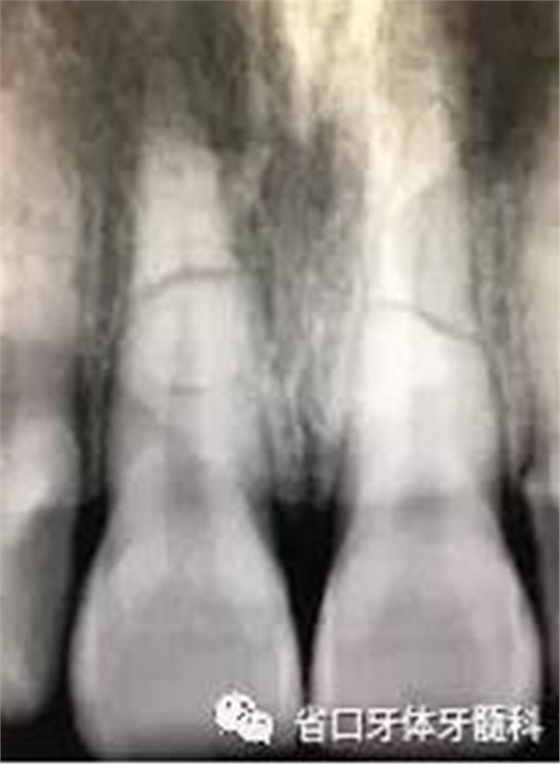

圖1:術(shù)前口內(nèi)照

X線片:11、21根中段見橫行根折線,無移位,根尖無明顯異常。

圖2 術(shù)前根尖片

CBCT:11、21頸部以下均見一完全性折裂線,兩牙折裂線均位于頜骨內(nèi)且斷端移位不明顯,相應(yīng)唇側(cè)骨板亦見斷裂且輕度移位。